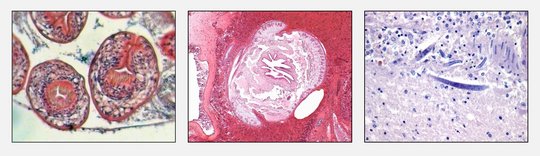

![Erregernachweis im Gewebe Erregernachweis im Gewebe: Mikroskopisch sichtbare Parasiten(bestandteile) [links: Kopfanlagen des dreigliedrigen Hundebandwurms (Echninococcus granulosus); mitte: Zungenwurm (Armillifer armillatus) Querschnitt; rechts: Fadenwurm (Halicephalobus) im Gehirn]](/fileadmin/_processed_/d/a/csm_ErregerImGewebe_Collage3Bilder_ea07831f44.jpg)

The National Reference Centre for Tropical Pathogens offers molecular biological methods for the detection of infectious agents in tissues.

In addition to the detection of viruses and bacteria by PCR according to our examination orders, molecular biological investigations can also be carried out in the field of parasitology (protozoa, helminths, pentastomids and arthropod larvae) after microscopy and morphological classification. The comparison of parasite sequences with a database often also provides information on the geographical region of infection.